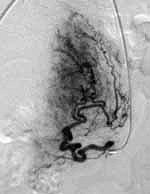

![]() |

| The post-UFE image shows arteries occluded for a reduction in blood flow to the fibroids. Image courtesy of Dr. Neal Joseph, Radiology Associates of Hollywood, FL. |